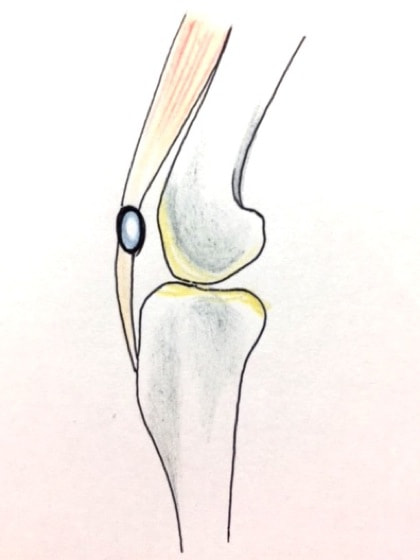

膝蓋骨脱臼

膝蓋骨が大腿骨遠位の滑車溝から内方または外方に転移する状態

膝蓋骨(膝の皿)が正常な位置から外れてしまう進行性疾患です。本症は先天性と後天性に分けられ、先天性のものでは、出生時からの膝関節周囲の筋肉、また骨の形成異常や靭帯の付着部の異常などが存在し、加齢とともにこれらが悪化することで、膝蓋骨の脱臼を招きます。後天性のものでは、打撲や落下などによる外傷性が原因で膝蓋骨周囲の組織に損傷が生じることで発症します。以下に詳しく説明します。症例はコチラから。